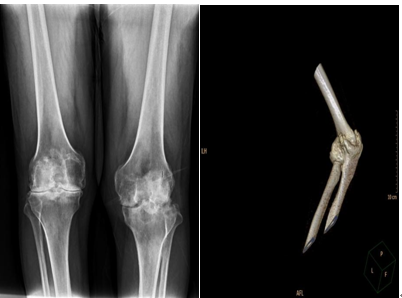

接诊唐先生后,李杨仔细地检查了患者的身体情况,根据病史,影像学资料,发现患者病程长,畸形重,受累关节多,右膝关节严重屈曲挛缩,外翻畸形,内侧副韧带严重松弛,左膝关节严重骨性屈曲强直,股部肌肉及小腿肌肉完全萎缩,双踝关节严重关节炎距骨坏死,跟腱挛缩,周围软组织条件非常差。“如此严重的病情是较为罕见的,患者最大的治疗难点已不是骨性结构的问题。由于20余年的屈曲畸形导致患者屈侧软组织严重挛缩,血管神经随之收缩,关节置换过程中容易产生损伤,矫形过程中难以完全伸直,只能在术中根据实际情况,随时调整方案。”李杨介绍说,“虽然手术难度极大,但我们有把握,也有信心处理好。”